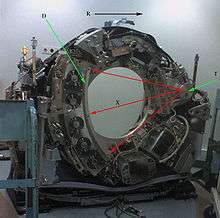

X-ray slice data is generated using an X-ray source that rotates around the object; X-ray sensors are positioned on the opposite side of the circle from the X-ray source. The earliest sensors were scintillation detectors, with photomultiplier tubes excited by (typically) cesium iodide crystals. Cesium iodide was replaced during the 1980s by ion chambers containing high-pressure xenon gas. These systems were in turn replaced by scintillation systems based on photodiodes instead of photomultipliers and modern scintillation materials (for example rare earth garnet or rare earth oxide ceramics) with more desirable characteristics.

Initial machines would rotate the X-ray source and detectors around a stationary object. Following a complete rotation, the object would be moved along its axis, and the next rotation started. Newer machines permitted continuous rotation with the object to be imaged slowly and smoothly slid through the X-ray ring. These are called helical or spiral CT machines. A subsequent development of helical CT was multi-slice (or multi-detector) CT; instead of a single row of detectors, multiple rows of detectors are used effectively capturing multiple cross-sections simultaneously. Systems with a very large number of detector rows, such that the z-axis coverage is comparable to the xy-axis coverage are often termed cone beam CT, due to the shape of the X-ray beam (strictly, the beam is pyramidal in shape, rather than conical).

In conventional CT machines, an X-ray tube and detector are physically rotated behind a circular shroud (see the image above right). An alternative, short lived design, known as electron beam tomography (EBT), used electromagnetic deflection of an electron beam within a very large conical X-ray tube and a stationary array of detectors to achieve very high temporal resolution, for imaging of rapidly moving structures, for example the coronary arteries. Cone-beam CT functionality is also an increasingly common function found in medical fluoroscopy equipment; by rotating the fluoroscope around the patient, a geometry similar to CT can be obtained, and by treating the 2D X-ray detector in a manner similar to a CT detector with a massive number of rows, it is possible to reconstruct a 3D volume from a single rotation using suitable software.

T: X-ray tube

D: X-ray detectors

X: X-ray beam

R: Gantry rotation